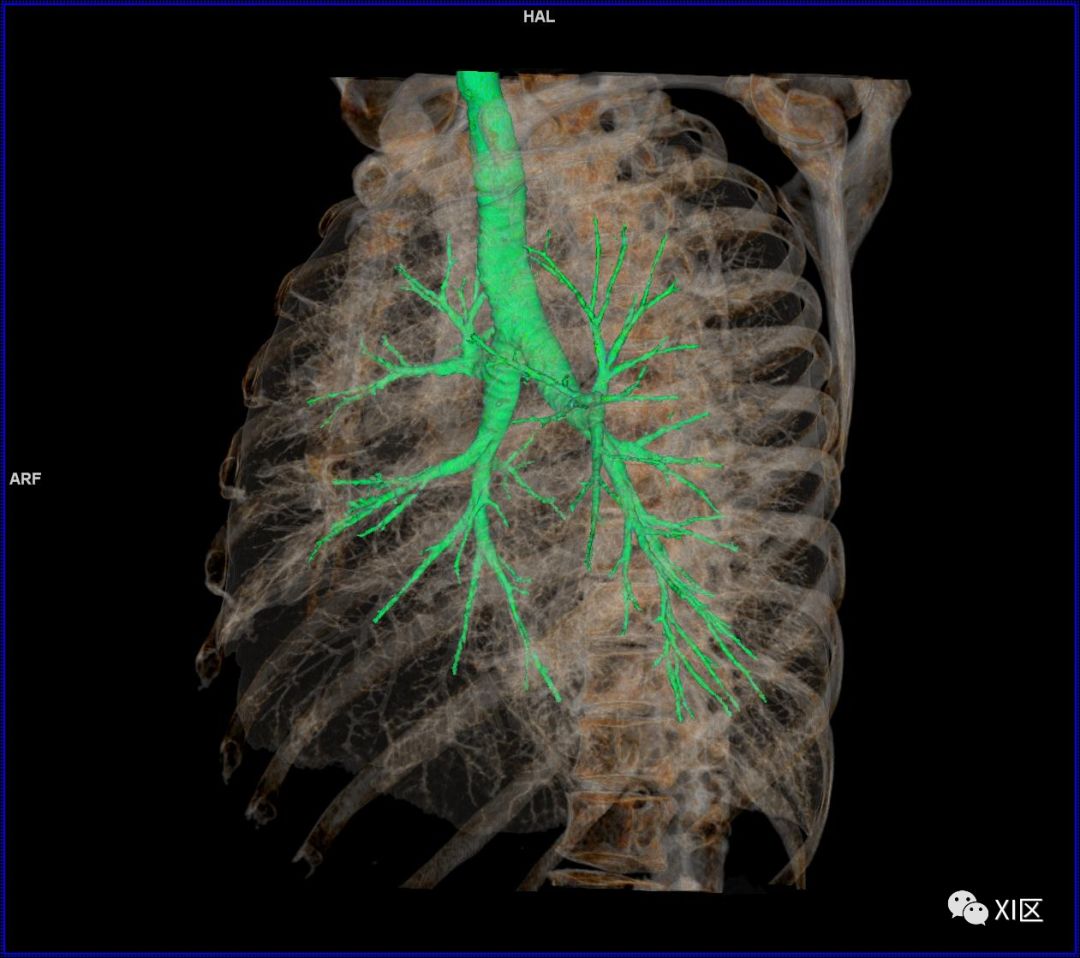

前后位,双侧位,后前位显示气道肺与胸部骨骼的关系

气管树

气管树与胸部其他结构的关系